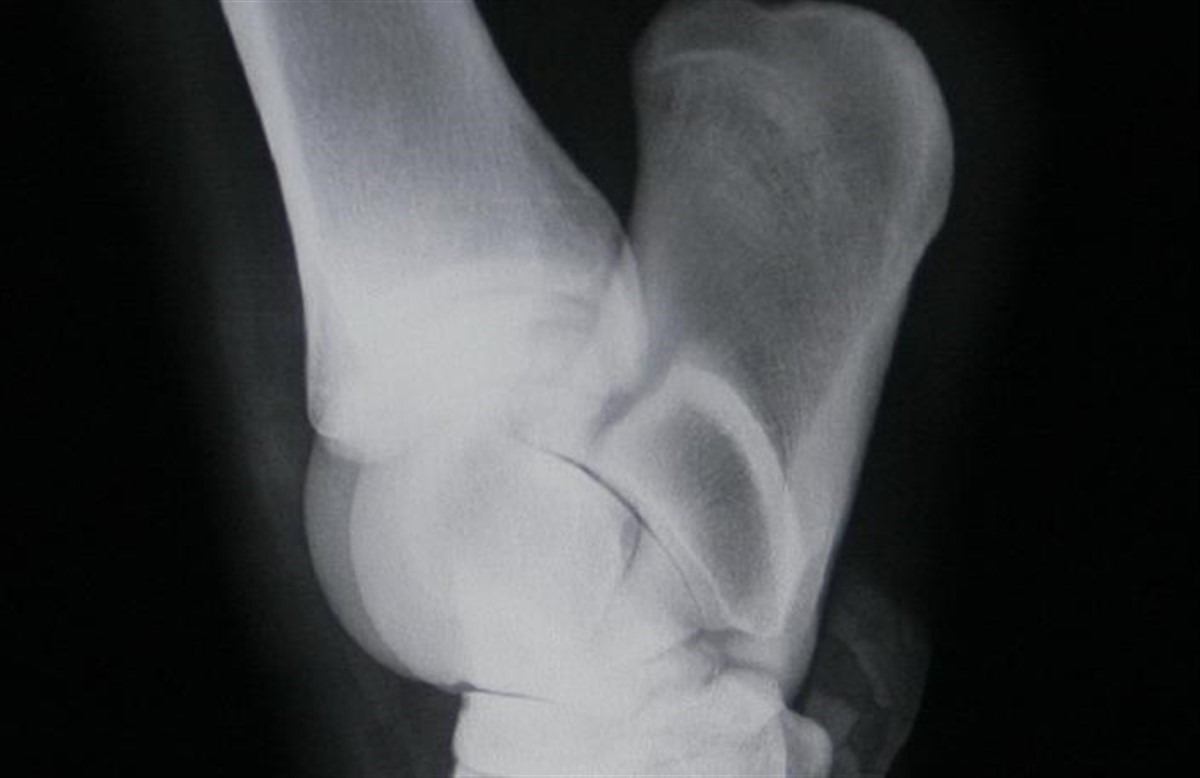

Jon vil gennemgå billeder af ben, ryg og hals, og illustrere diverse senarier bl. a. vedrørende basal fragment (mus), OCD, forkalkning af halshvirvler, kissing spine osv.

- Hvornår kan/skal hesten opereres for mus og hvornår kan man undlade det?

- OCD - hvad er det, hvor arveligt er det og hvad betyder det for holdbarheden?